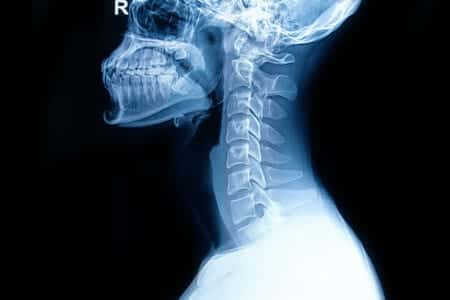

Neurosurgery Experts Discuss Cervical Spine Injury Caused by Vehicle Rollover Accident

This case involves a young female who was involved in a significant accident in which she rolled her SUV while traveling down the highway. After the accident, she was transported to the emergency room where imaging studies were performed. The images that were taken weren’t conclusive of a cervical fracture, and the woman was discharged within the day. During her time in the hospital, she complained of severe back pain, however she was able to walk with assistance. As was later determined, the woman had sustained a serious cervical fracture which went undiagnosed. Within hours of being discharged, the patient developed permanent paralysis. It is alleged that the ER physicians failed to provide a thorough and adequate workup, such as ordering additional imaging studies, or conducting testing to ensure no cervical fracture or major injury was present, which resulted in the loss of the opportunity for neurosurgical intervention. It was also alleged that timely neurosurgical intervention for this patient would have prevented the patient’s paralysis.